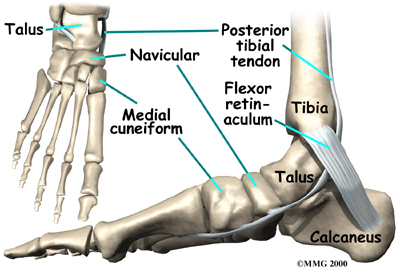

The navicular bone of the foot is one of the small bones on the mid-foot.

The bone is located at the instep, the arch at the middle of the foot. One of the larger tendons of the foot, called the posterior tibial tendon, attaches to the navicular before continuing under the foot and into the forefoot. This tendon is a tough band of tissue that helps hold up the arch of the foot. If there is an accessory navicular, it is located in the instep where the posterior tibial tendon attaches to the real navicular bone.

Posterior Tibial Tendon